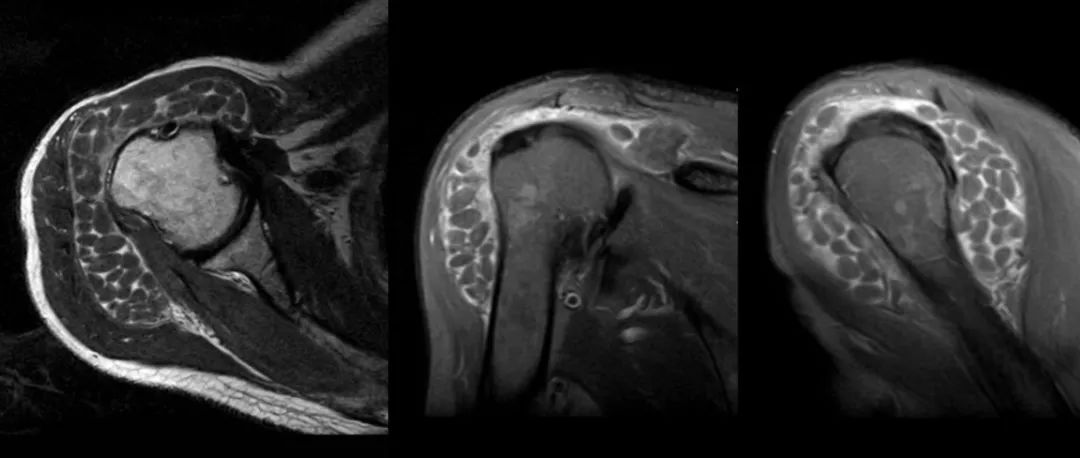

滑囊,也称为滑膜囊,是人体内的一种结缔组织扁囊,在人体压力较大或者摩擦比较频繁的大关节附近存在,滑囊中含有少了滑液,可以减轻压力,增加关节间的润滑。人体出现滑囊炎的原因有多种的情况,但最主要的原因还是因为长期、反复、持续性的摩擦和压迫,导致滑囊劳损,形成炎性并伴随疼痛,从而产生滑囊炎。但是也有部分人群会因为急性压迫、感染病菌、痛风等原因患上滑囊炎。滑囊炎的六大症状01 疼痛对于患有滑囊炎的人来说,疼痛时最为常见的症状。滑囊炎导致疼痛的部位通常发生在肩部、肘关节、髋关节甚至是膝关节、脚后跟等部位,这些部位产生的疼痛对人体运动影响也是较大的。这种疼痛通常是钝痛,同时也会随着运动加重痛感。...